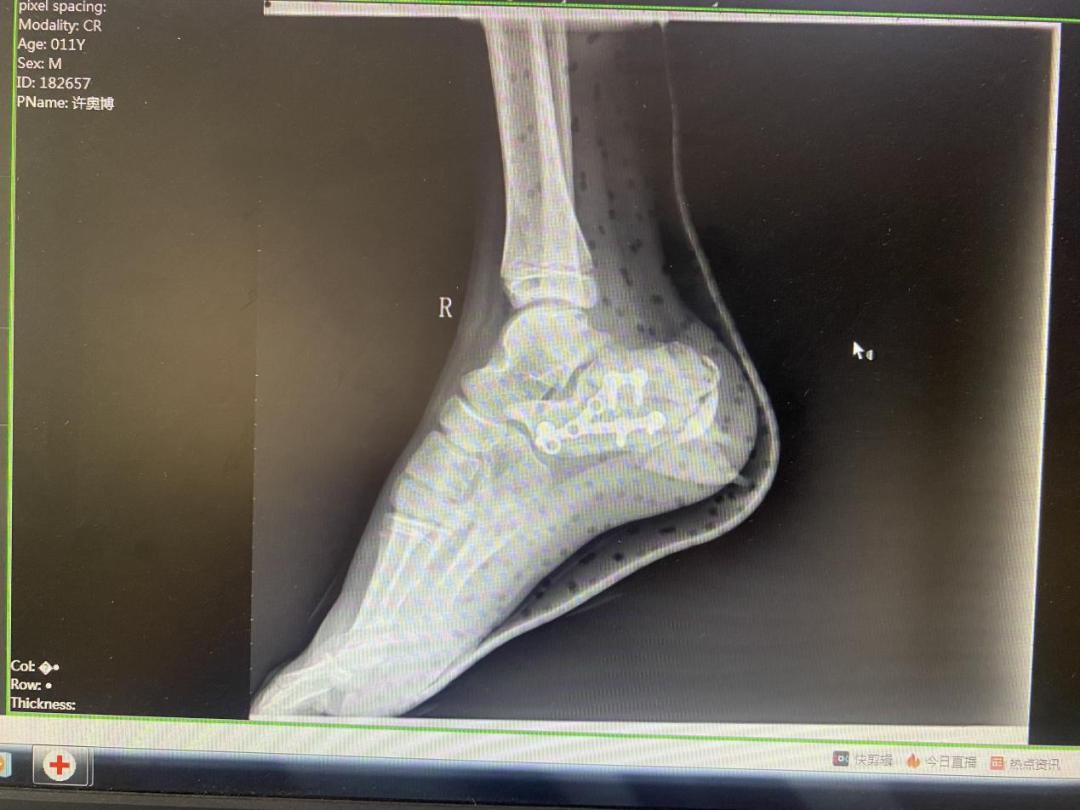

术后X线